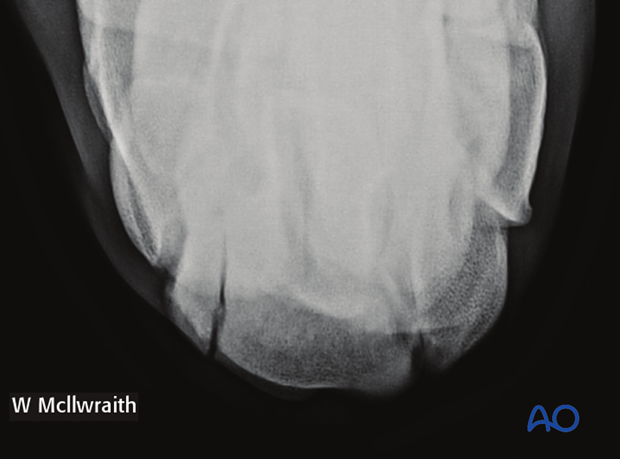

This radiographic view shows a sagittal fracture of the radial facet of the third carpal bone in the flexed dorsoproximal dorsodistaloblique (flexed D30Pr-DDiO) (skyline) view.